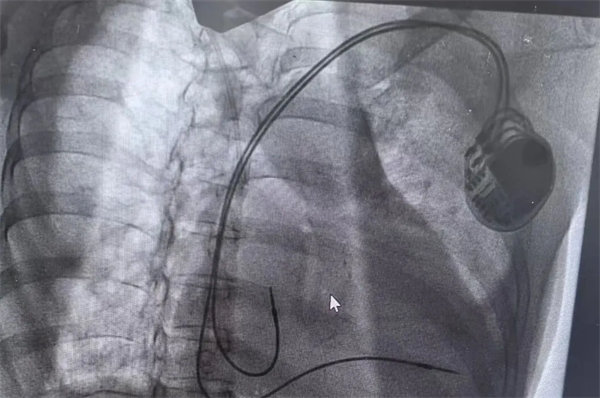

在充分術前準備和家屬的理解支持下,心血管內一科主任翟向偉副主任醫師、陳萬林副主任醫師及介入導管室團隊為患者實施了雙腔心臟永久性起搏器植入術。通過左側腋靜脈入路,精準、輕柔操作順利植入起搏器。術后經過醫護團隊的精細診治,起搏器囊袋如期愈合,患者可自由活動,生活質量得到有效改善。患者及家屬露出了久違的笑容。